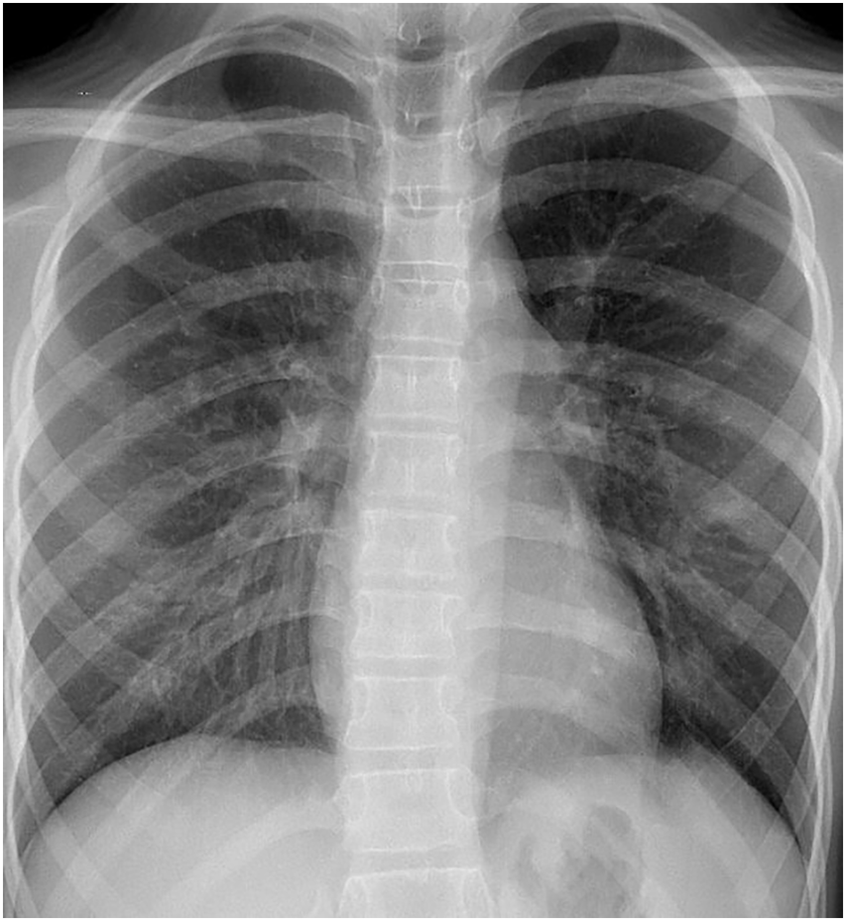

Figure 1

Chest plain radiograph of the child at the time of admission; no basis for pulmonary arteriovenous fistula was found.

A post-admission physical examination revealed cyanosis of the mouth and lips. Routine physical examinations of the nervous system, heart, lungs, and abdomen indicated no obvious cyanosis of the limbs, no noticeable abnormalities, no clubbing of the fingers or limbs, and no murmurs on cardiopulmonary auscultation. Upon admission, under room air, the patient's transcutaneous oxygen saturation was between 87% and 89%, measured using different pulse oximetry devices. In addition, under room air, results of blood gas analysis revealed that PaO2 was 121 mmHg, with 89.7% oxygen saturation. There were no abnormalities in routine laboratory tests, and the results are shown in Table 1. Chest radiographs and 12-lead EKGs are normal (as Figures 1, 2).